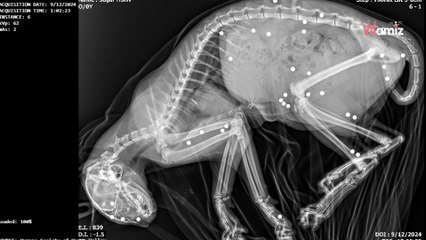

Un couple a découvert un petit chaton abandonné seul dans une cour dans le Nevada.